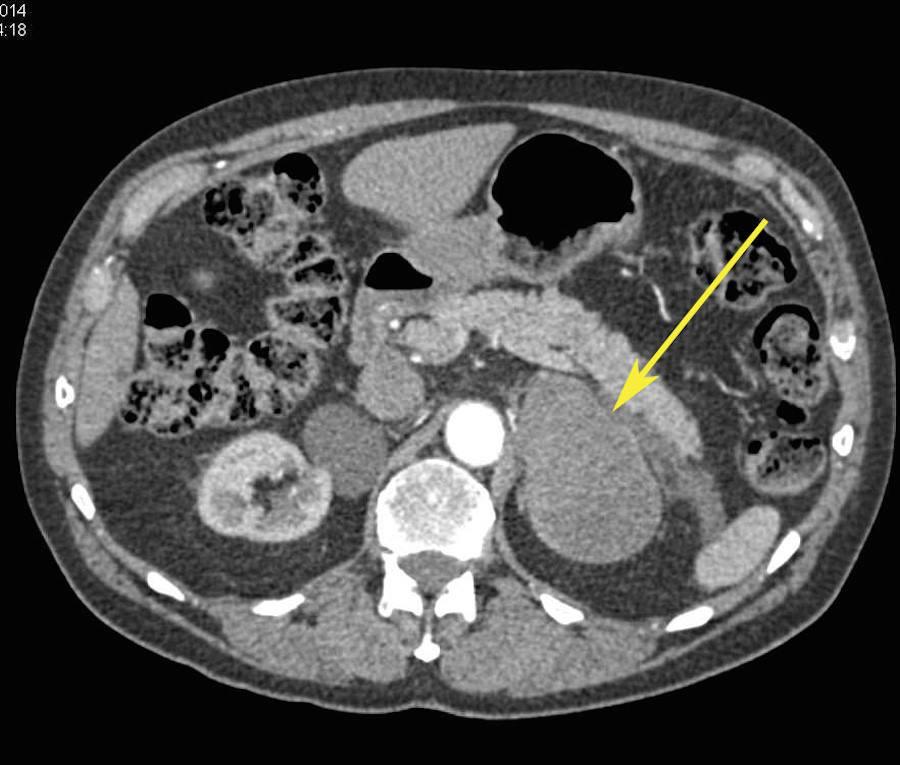

La hemorragia suprarrenal es una entidad infrecuente que puede ser uní o bilateral.

Cuando es unilateral suele ser clínicamente silente y en la mayor parte de los casos se diagnostica de forma incidental.

Sin embargo, la hemorragia bilateral por lo general desencadena una insuficiencia suprarrenal aguda, a veces dando como resultado el coma o la muerte si la terapia de reemplazo de esteroides no se administra con prontitud.

Las causas de hemorragia suprarrenal se dividen en traumáticas (la mayoría unilaterales y derechas) y espontaneas, agudas y crónicas.